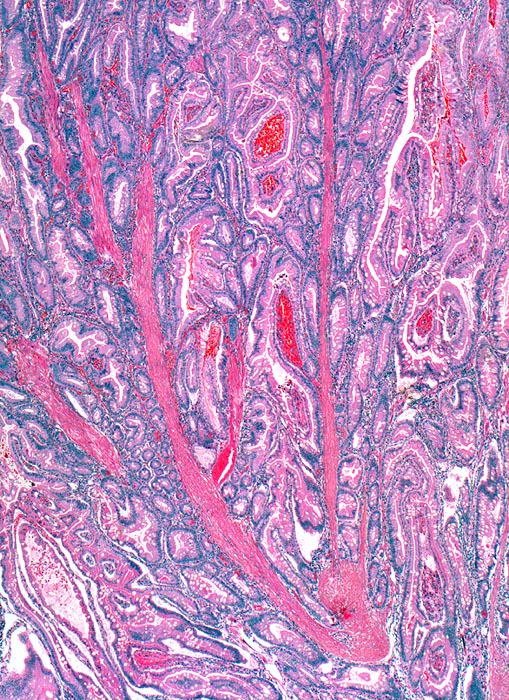

AP/ Peutz-Jeghers Polyp, Dünndarm

Peutz-Jeghers Polyp, Dünndarm

Jejunum

Pathologischer Befund